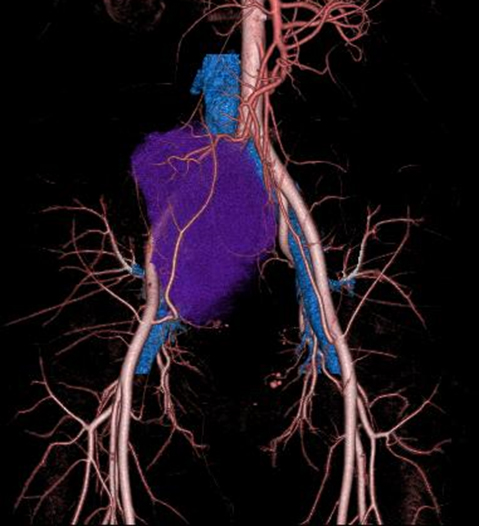

Volume rendering画像では内腸骨動脈領域・回結腸動脈から腫瘍への多数の流入血管を認めた(Fig. 2).

Contrast enhanced CT findings·volume rendering: The branches of the right internal iliac artery and the ileocolic artery were the main feeders.